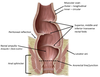

Postganglionic sympathetic fibers (they synapsed in the ganglion) leaving the sympathetic chain and joining a sacral nerve (S1). Will leave the pelvis with to go to the legs to nnervates blood vessels, sweat glands, hair follicules, etc.

Red arrow?

Sacral splanchnic nerves - Preganglionic sympathetic fibers (they came down the chain) which will synapse in the inferior hypogastric plexus. They provide sympathetic innervation to the pelvic organs.